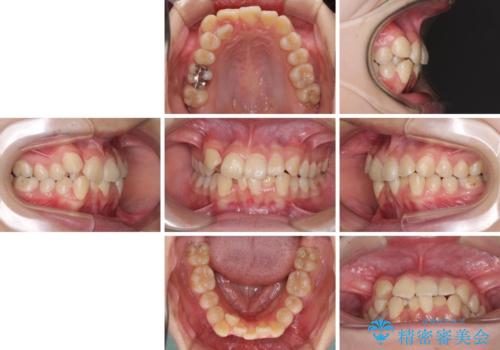

- 上下の八重歯と前歯のデコボコを気にして来院された患者様です。

右上の八重歯が特に著しく、上顎正中が右側にシフトしていました。

デコボコが強いため小臼歯4本を抜歯し、上顎正中を左側に移動させるために補助装置を使用して、ワイヤー装置にて矯正治療を行うこととしました。